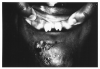

Concrescence represents the joining of adjacent teeth via the cementum with obliteration of the intervening periodontal ligaments. Concrescence is usually found in two teeth, rarely in three or more. The clinical appearance of the condition is shown in Figure 41 and the appearance on a radiographic image in Figure 42.

Figure 41 - Clinical Concrescence

Figure 41

Figure 42 - Radiographic Concrescence

Figure 42